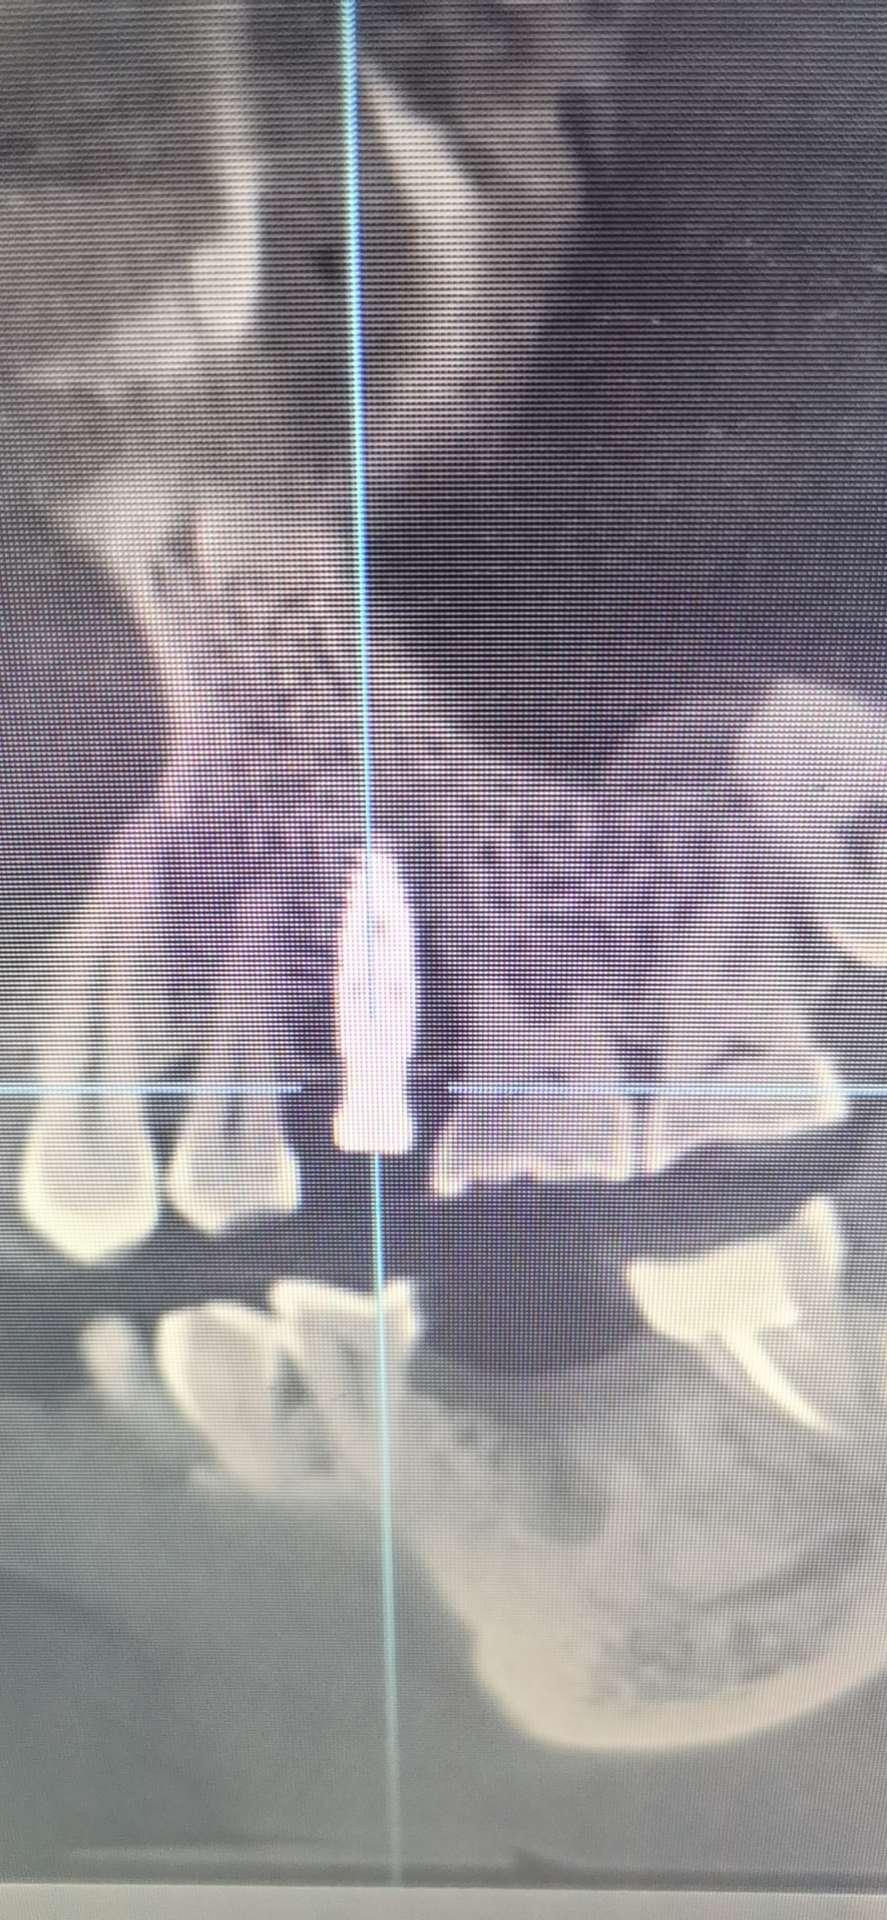

2021年11月28日:刚去复诊了,左上门牙术后一切正常,左后槽牙微疼,脸肿了,用手摸上去有一硬包。经医生诊断后说无大碍,只要遵医嘱服药,很快就会康复。十二月三号上午拆线。

2021年12月初某日:没到约定的12月3日就拆了线,毫无感觉,现在正常吃饭正常刷牙,近日不用去看医生了。目前有一个问题,左上缺牙时间太久,下牙长上来了,医生建议正畸,把下牙压回去,我暂时没做处理,等等看……